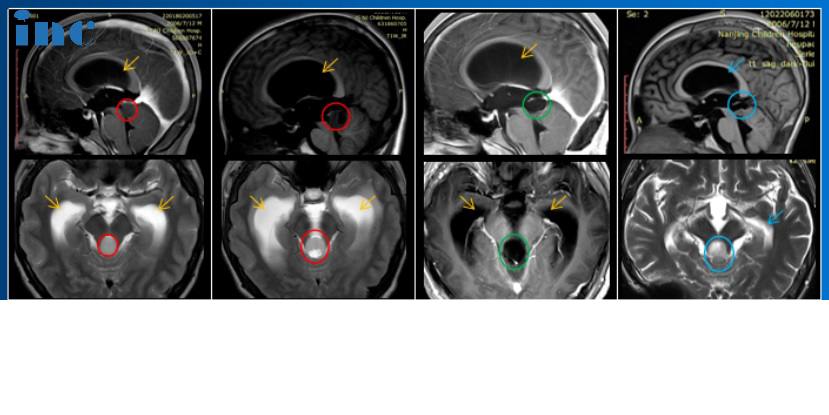

14岁的小永查出脑干胶质瘤,影像片子显示:脑干-中脑顶盖,伴有幕上脑室扩张积水,脑室及大脑实质已经受压变形。在与患者家属沟通中我们得知,小永2018年就出现过轻微头痛、头晕,去医院检查发现脑干肿瘤,并伴有梗阻性脑积水。小永的父亲咨询了很多专家。“每次都说毛细胞星形细胞瘤一般不长,观察就行,但是后来我然后一次去找他们的时候,我说症状太重,不行就做手术,他们然后和我说实话,因为做手术风险过大,所以说建议你观察……”这一拖就是2年多,孩子的病情越来越严重。

巴教授仔细研究小永的相关资料后表示:“已经有很明显的手术指征。我想知道为什么他还没有得到治疗,因为病变是从2018年就知道了。无论如何,我强烈建议不要给病人提供脑室腹腔分流术,因为这样一来,他将一直依赖于这个分流术。”小永的父母觉得再不能拖下去了,经过反复考量后,开始准备带孩子去德国找巴教授做手术,在INC协调和帮助下以较快的速度办完手续,不到一个月的时间内到达德国做上了手术。

手术结果令人欣喜,小永的肿瘤得到近全切除,病理结果为毛细胞型星形细胞瘤,这是一种预后较好的胶质瘤,全切或近全切后复发率低。

2022年7月,术后已经过了1年半,我们对小永进行随访时得知他已经凭借的中考成绩,考入示范高中,其中体育成绩还获得了满分,完全看不出来曾经做过开颅脑干手术。